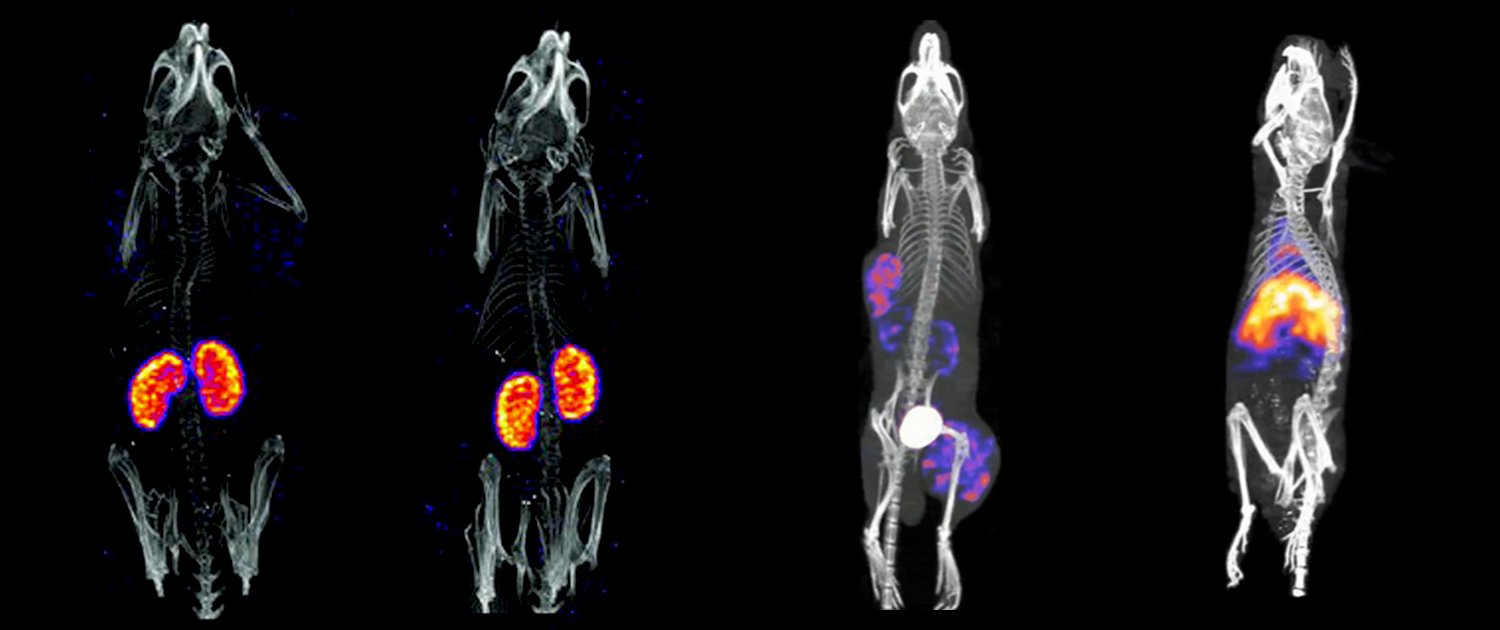

Micro-PET

Micro-PET, or micro-Positron Emission Tomography, is an imaging technique that uses radiolabeled molecules to track biological processes in animals. In this technique, animals are injected with a radiotracer that emits positrons. When the positrons collide with electrons in the tissue, they release gamma rays, which are detected by the scanner to create a 3D image of the body. Micro-PET has applications in drug development, cancer research, and neurology. For example, micro-PET can be used to study drug metabolism and distribution in vivo, to track the progression of tumors, and to study neurodegenerative diseases.

Micro-SPECT

Micro-SPECT, or micro-Single Photon Emission Computed Tomography, is another imaging technique that uses radiolabeled molecules to track biological processes. In this technique, animals are injected with a radiotracer that emits gamma rays. The gamma rays are detected by a scanner to create a 3D image of the body. Micro-SPECT has applications in the study of cardiovascular diseases, cancer, and neurological disorders. For example, micro-SPECT can be used to study blood flow in the heart, to track the spread of cancer, and to study brain activity.